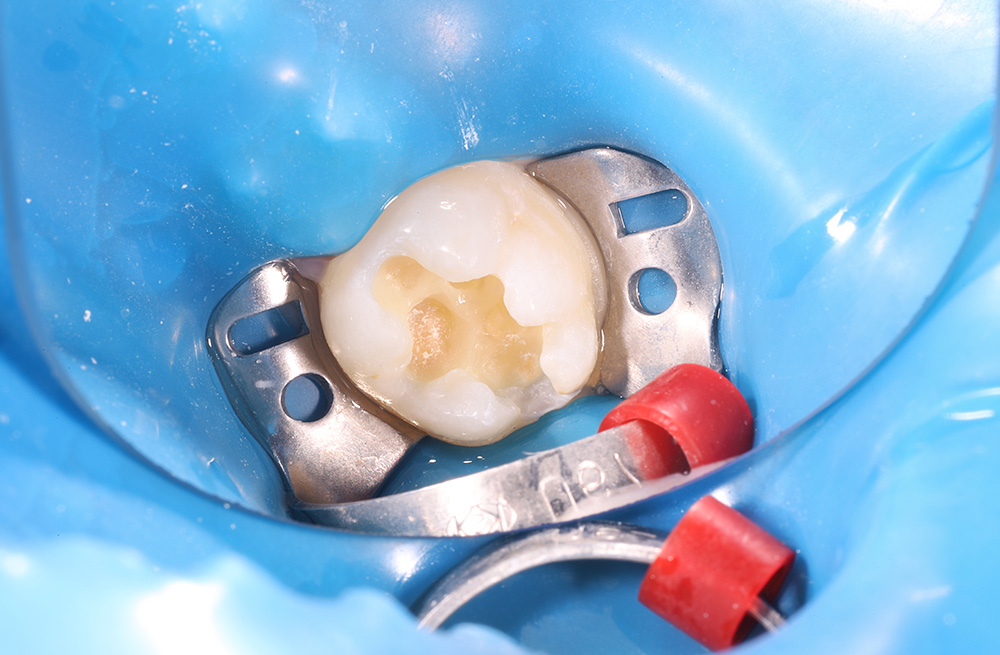

Лечение кариеса на жевательной поверхности постоянного зуба у подростка